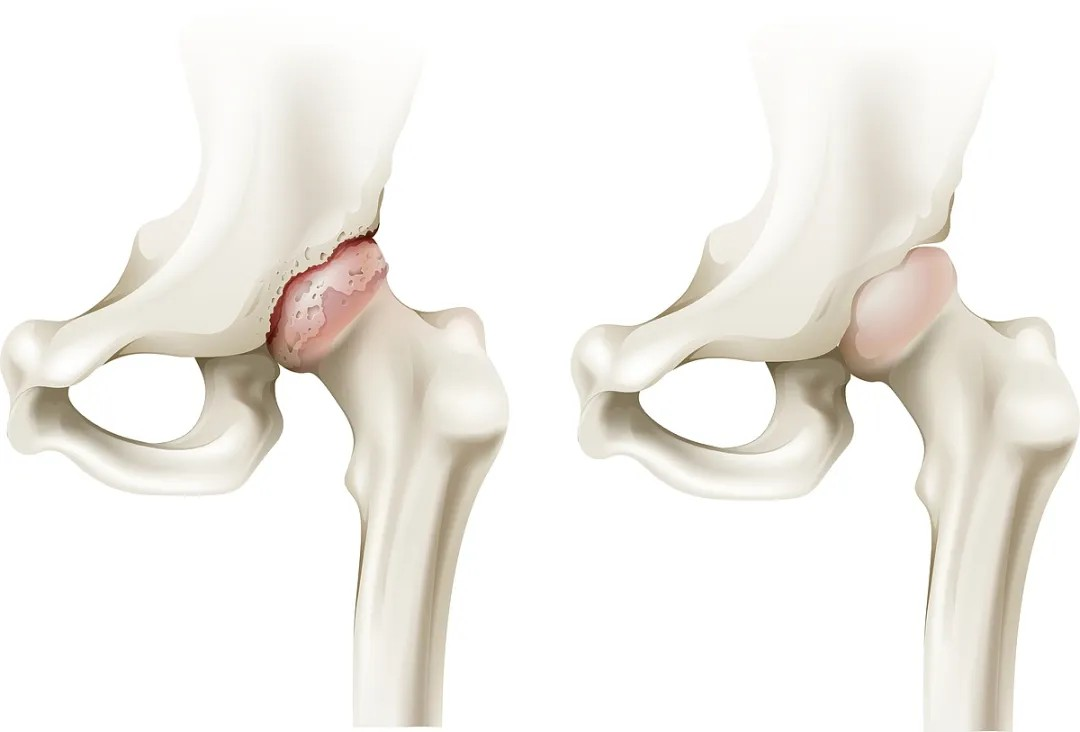

最近骨科中心入住了一位120转送来的71岁老年男性患者,需要对他行股骨颈骨折闭合复位内固定术,但是这位老先生有严重的肾功能衰竭,还在其他医院进行透析,并且心脑血管都有严重的问题,多次脑梗病史,心脏放过多枚支架,术前检查心肌酶显著增高,下肢还发现了静脉血栓。在某三甲医院住院期间,由于围术期风险过高,医生不建议手术。但对于髋部骨折的老年人来说,早一天手术,就意味着更良好的预后。

按照许主任本人通俗的说法,这是典型的手术指征明确、但病人基础条件恶劣的病例。对于麻醉提出了极大的挑战;由于患者透析以及下肢血栓抗凝的需要,下肢手术常用的椎管内麻醉出血风险太大,无法进行。而采用全身麻醉,患者肾衰以及心脑血管风险又会给围术期管理带来极大挑战。通过术前详细的评估,许主任最终决定对该患者实施单纯神经阻滞麻醉。考虑到抗凝带来的出血风险,优化了神经阻滞入路,采用了对凝血功能要求相对低的超声引导下前路腰丛+骶旁坐骨神经联合阻滞,精准覆盖术区,患者在清醒但完全无痛的状态下顺利完成手术,术后直接转回普通病房。同时,神经阻滞镇痛效果会持续十余个小时,也解决了术后镇痛问题。